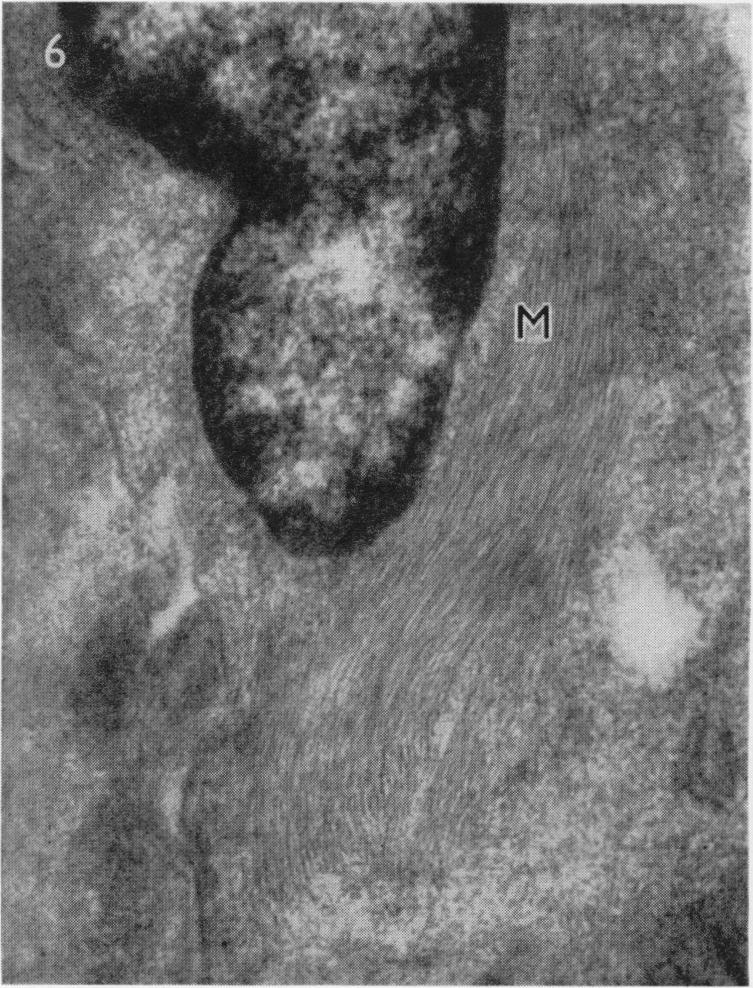

AN ELECTRON MICROSCOPE STUDY OF HUMAN BREAST CELLS IN FIBROADENOSIS AND CARCINOMA.

Br J Cancer. 1964 Dec;18(4):682-5. doi: 10.1038/bjc.1964.78.